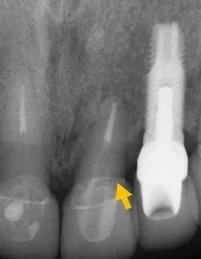

X光片檢查,門牙已斷裂

比較最初與植牙後的X片,可見到左邊與自然牙間完整保留原來的骨質(水平線),右邊與植牙間更誘導再生出更多的骨質(箭號),如此牙齦不會萎縮,才能塑型到漂亮。